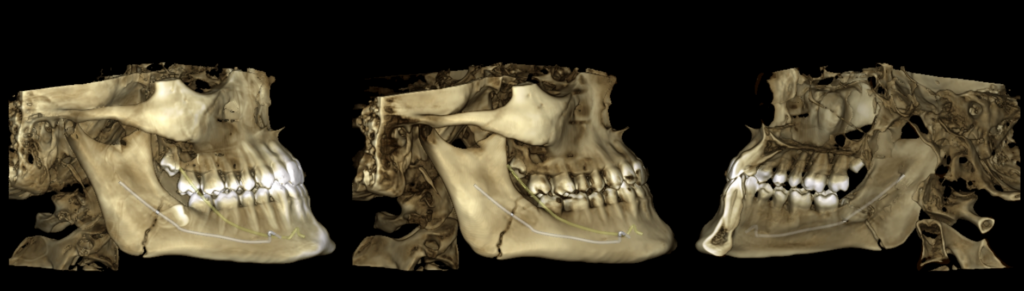

En las reconstrucciones 3D se representa de manera didáctica Fractura mandibular. (Figura 4).

RECONSTRUCCIÓN 3D